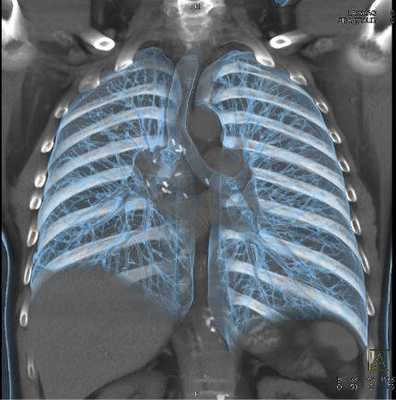

КТ мягких тканей грудной клетки

Оценка состояния мягкотканных элементов, органов грудной клетки и пространства между ними происходит с использованием контрастной МСКТ. При попадании раствора в кровь на снимках и 3D-модели, если она создавалась, четко прослеживается сеть сосудов, питающая каждый орган. КТ визуализирует структурные изменения органов средостения, выявляет патологические процессы в легких, отражает состояние вен и артерий данной области.

Мультиспиральная КТ грудной клетки, 3D-реконструкция

Специалисты выделяют в средостении три области: центральное (сосудистое пространство с перикардом и его содержимым, сосудами и лимфатическими узлами), переднее (жировая клетчатка, вилочковая железа, внутренние грудные артерии и лимфоидные ткани) и заднее (трахея, пищевод, нисходящая часть грудной аорты, лимфоузлы и паравертебральные пространства грудной клетки). Соответственно, все патологические процессы, которые протекают в данных зонах, могут быть видны.